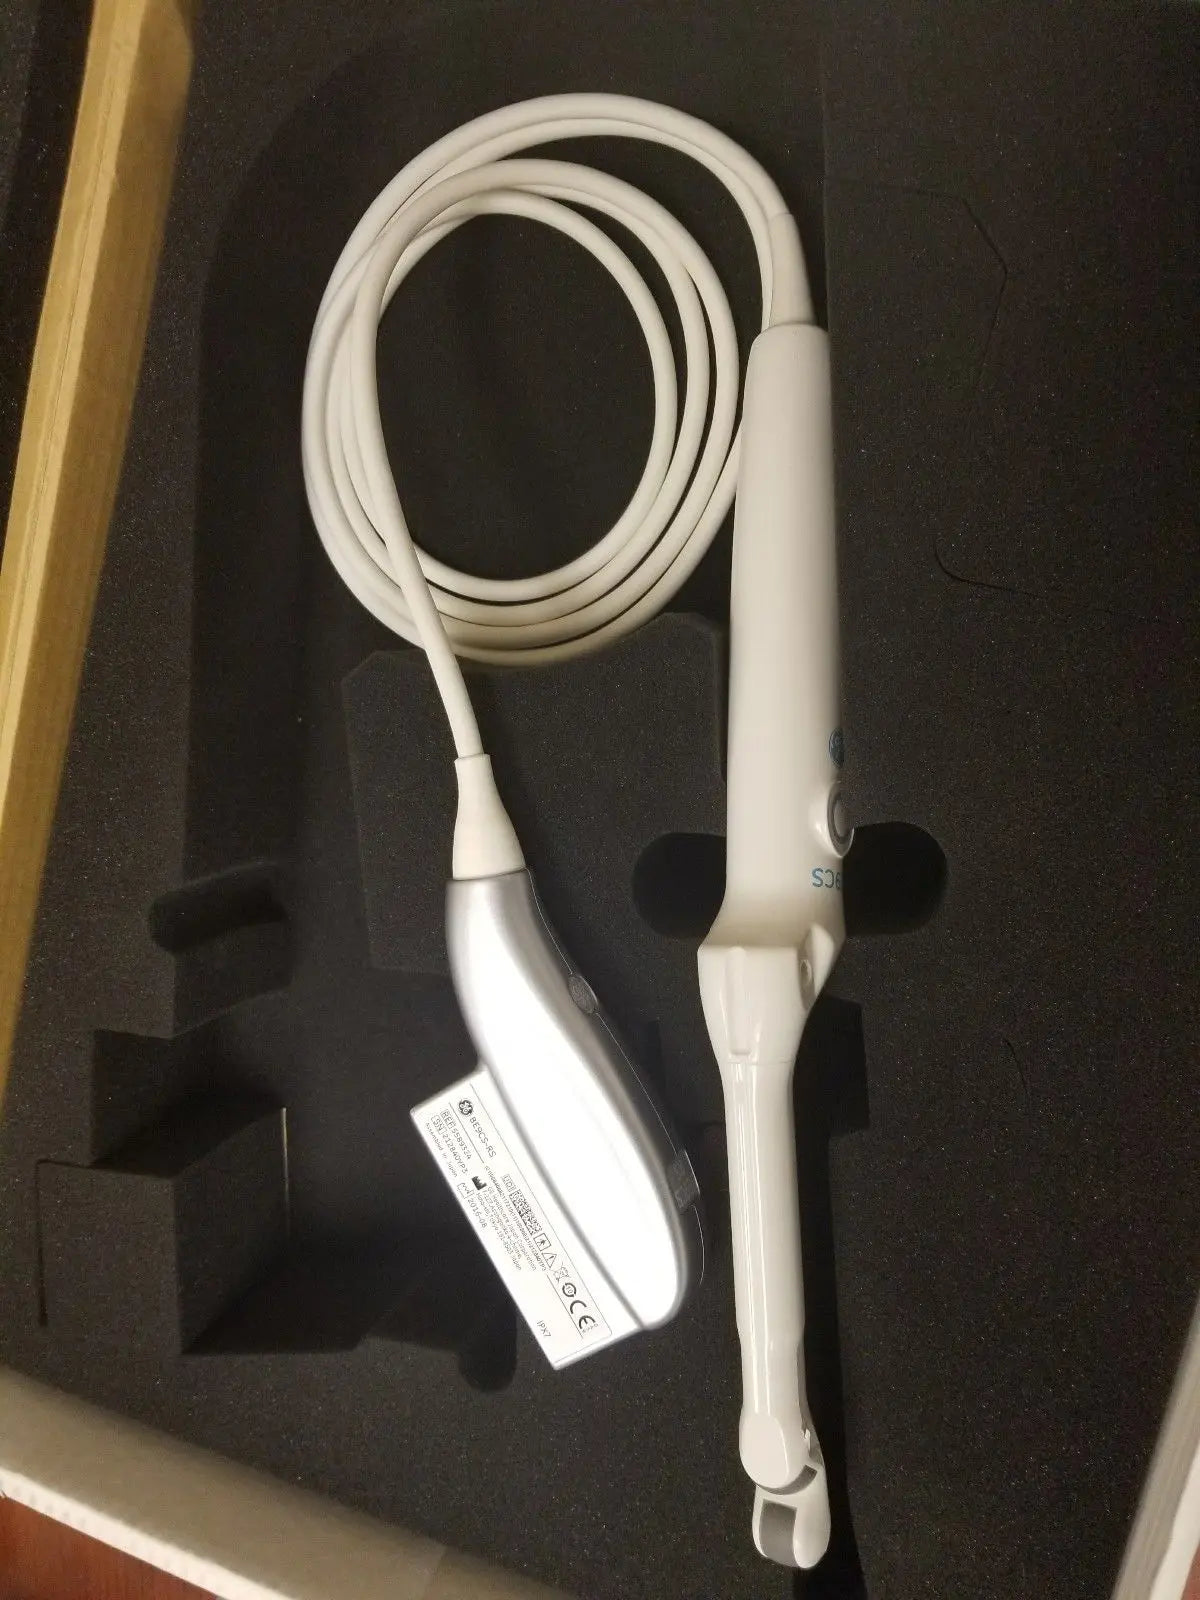

DIAGNOSTIC ULTRASOUND MACHINES FOR SALE

2017 GE IC9 -RS probe for GE Ultrasound

Sale price$ 8,395.14